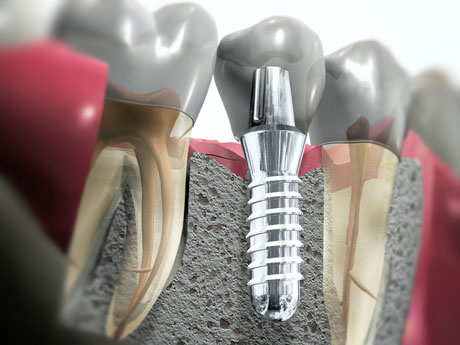

Виды имплантации зубов

В этой статье мы расскажем Вам про: классическую, базальную, а также экспресс имплантацию зубов.

Когда в зубном ряду по той или иной причины появляется пустое место (удален зуб), то следует заместить пустое место, потому что соседние зубы будут стараться закрыть дефект и мы получим кривой зубной ряд.